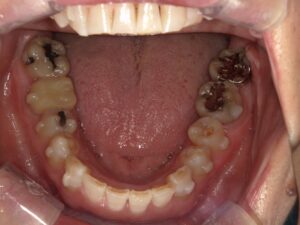

下顎の歯並びの変化

舌の置き場にも少しゆとりが出てきました。